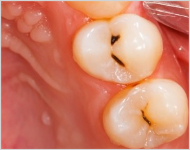

除净病变组织,保护牙髓和健康牙齿组织,建立良好的固位形和抗形,以免造成继发龋。

早龋,一次消毒即可进行补牙,中龋或深龋,则需m三至五次,如果涉及到牙神经则需根管治疗。